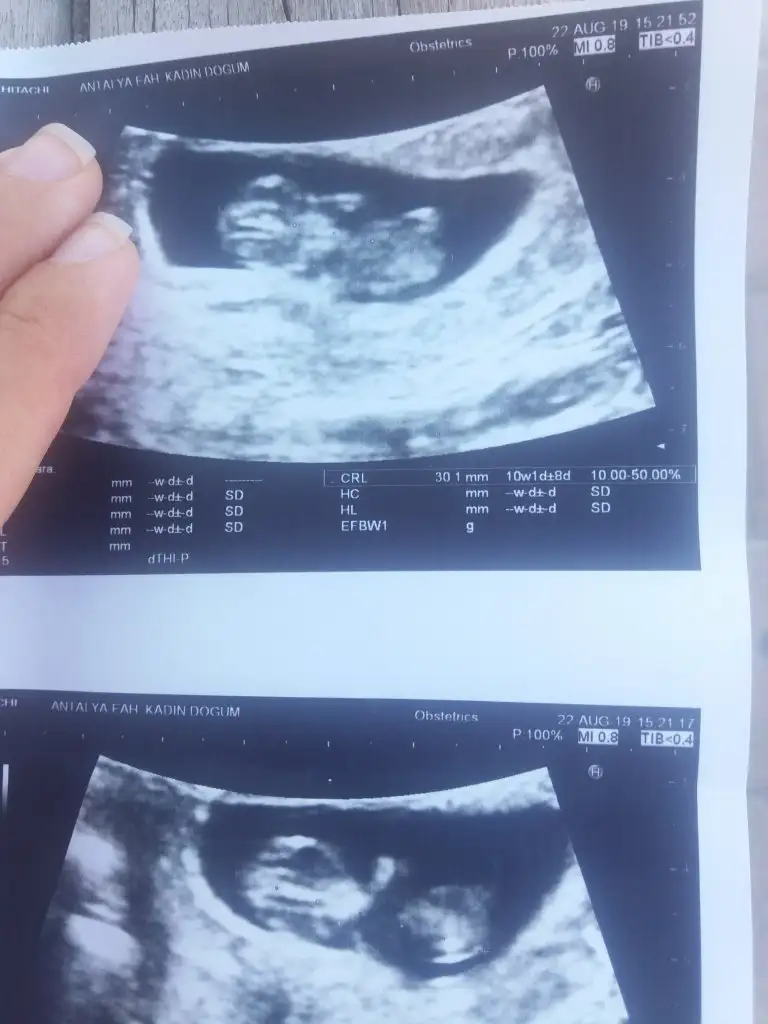

Kaç haftalık usg erkek diyorumBirde bu var net degil mi acaba

Kaç haftalık usg erkek diyorum

ErkekKızlar yeni görüntü 12+4 tahmin rica edebililirmiyim

Usg hic net degil cnm dr lar genelde bu haftalarda erkekse tahminde bulunuyorlar ama inan ben bisey goremedim icimden kiz demek gecti ama dedigim gibi usg ye gore tahmin degilSat 9+2 usgye gore 10 hftalik. Doktor kucuk bi tahminde bulundu. Siz de bi tahminde bulunurmusunuz